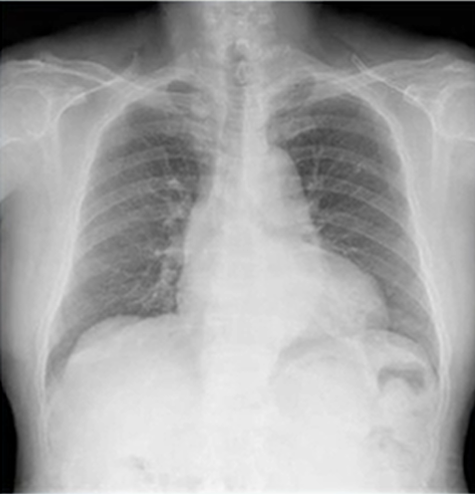

難易度は高めだが、肺腺癌レントゲン写真(X-p)

医師が胸部レントゲンで読影できるかで患者さんの寿命を大きく変えてしまうことがあります。なのでいつになっても医師は実力を高めるために努力が必要になります。本日のレントゲンで肺癌を疑うことはできるでしょうか?

今回のレントゲン(X-p)写真では左下肺野の心臓裏に結節影(肺野から左横隔膜へ走る白い陰影がおかしいことから推測していく)があることから疑うことができます。CTにて精査案件です。